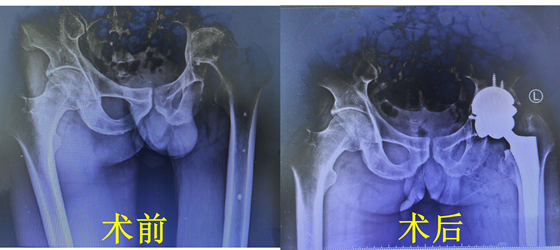

科室名称:骨科

湘雅常德医院骨科成立于2017年,经过7年的学科建设...